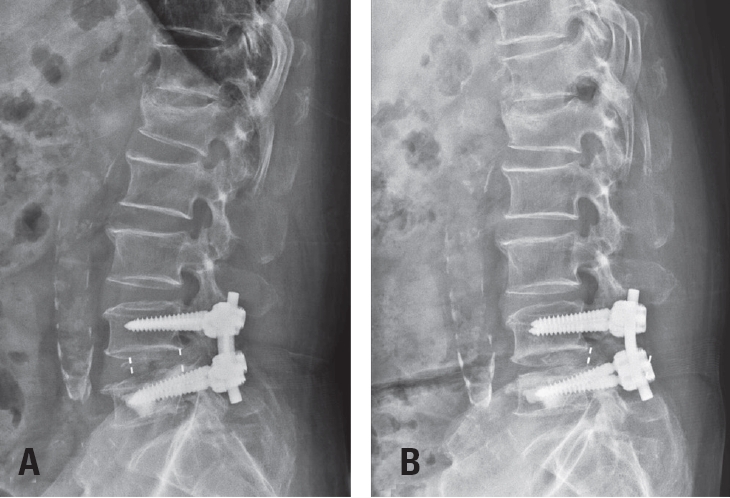

Postoperative imaging was essential for evaluating surgical outcomes. Standard radiographs and computed tomography (CT) scans were used to assess screw position and integrity. Mechanical failures—including pull-out and screw loosening—were identified by the appearance of a halo around the screw, indicating loss of fixation.10) Fig. 1 shows a typical pull-out, where the screw disengages from the vertebral body, whereas Fig. 2 demonstrates screw loosening, identified by the halo sign on CT imaging.

Fig. 2.

Computed tomography scan showing screw loosening, identified by a visible halo around the screw. The arrow highlights the halo sign.

Fig. 2. Computed tomography scan showing screw loosening, identified by a visible halo around the screw. The arrow highlights the halo sign.